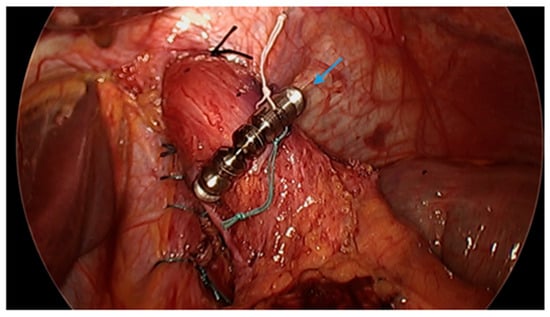

Figure 6.

Endoscopic images reveal a 3 cm hiatal hernia (arrows, top left) and Los Angeles Grade B esophagitis (arrows, top right) in the lower third of the esophagus with narrow-band imaging in a patient post-sleeve gastrectomy with symptoms of gastroesophageal reflux disease. The patient eventually required Roux-en-Y gastric bypass (arrow, bottom) and concomitant hiatal hernia repair, as demonstrated on upper gastrointestinal series.

Conversion from SG to RYGB is ultimately necessary for some patients with refractory GERD post-SG (Figure 6). There are robust data that conversion to RYGB is very effective for the treatment of GERD, as detailed in Table 2, in addition to its beneficial effects on weight loss and other comorbidities (i.e., diabetes, hypertension, dyslipidemia). In a recent retrospective study by MacVicar et al., 4412 patients required revisional surgery due to GERD, which comprises 24% of all conversion procedures [71]. SG was the original surgery in 80.1% of cases and Roux-en-Y was the revisional surgery in 84.4% of cases [71]. However, conversion from SG to RYGB is not without additional risk. In a recent study with matched cohorts of 5912 patients, an increase in re-admissions, intervention, conversion to open surgery and operative time was documented in the group which underwent conversion from SG to RYGB compared to primary RYGB. There were no significant differences in mortality or complications noted between the two groups. In a study by Dang et al., conversion from SG to RYGB compared to primary RYGB was associated with an increased rate of serious complications (7.2% vs. 5%, p < 0.001), including anastomotic leaks, bleeding and reoperation, although no significant difference in mortality between the two groups was demonstrated in the study [72].

Many studies reveal significant improvement in GERD symptoms and the use of acid suppression medications following conversion to RYGB. Studies by Langer et al. and Gautier et al. both reported that all patients were able to discontinue acid suppressive medications [73,74]. Parmar et al. revealed that 80% of patients discontinued acid suppressive medications whereas Hendricks et al. documented that 75% of patients had a complete resolution of GERD with conversion to RYGB [75,76]. A study by Strauss et al. concluded that 80.2% of patients who underwent conversion to RYGB had improvement in GERD symptoms [77].

The average rate of conversion from SG to RYGB due to GERD is approximately 5–10% [26,30,78]. In the SLEEVEPASS trial, the rate of conversion to RYGB was noted to be 6% [78]. In the SM-BOSS trial, the reported rate of conversion to RYGB was 9% [26]. In a meta-analysis of 46 studies by Yeung et al., 4% of patients underwent conversion to RYGB [30]. In a review of 73 cases, Langer et al. reported a conversion rate of 11% [73]. Some studies report a higher rate of conversion, although these studies had limitations [75,77,79].